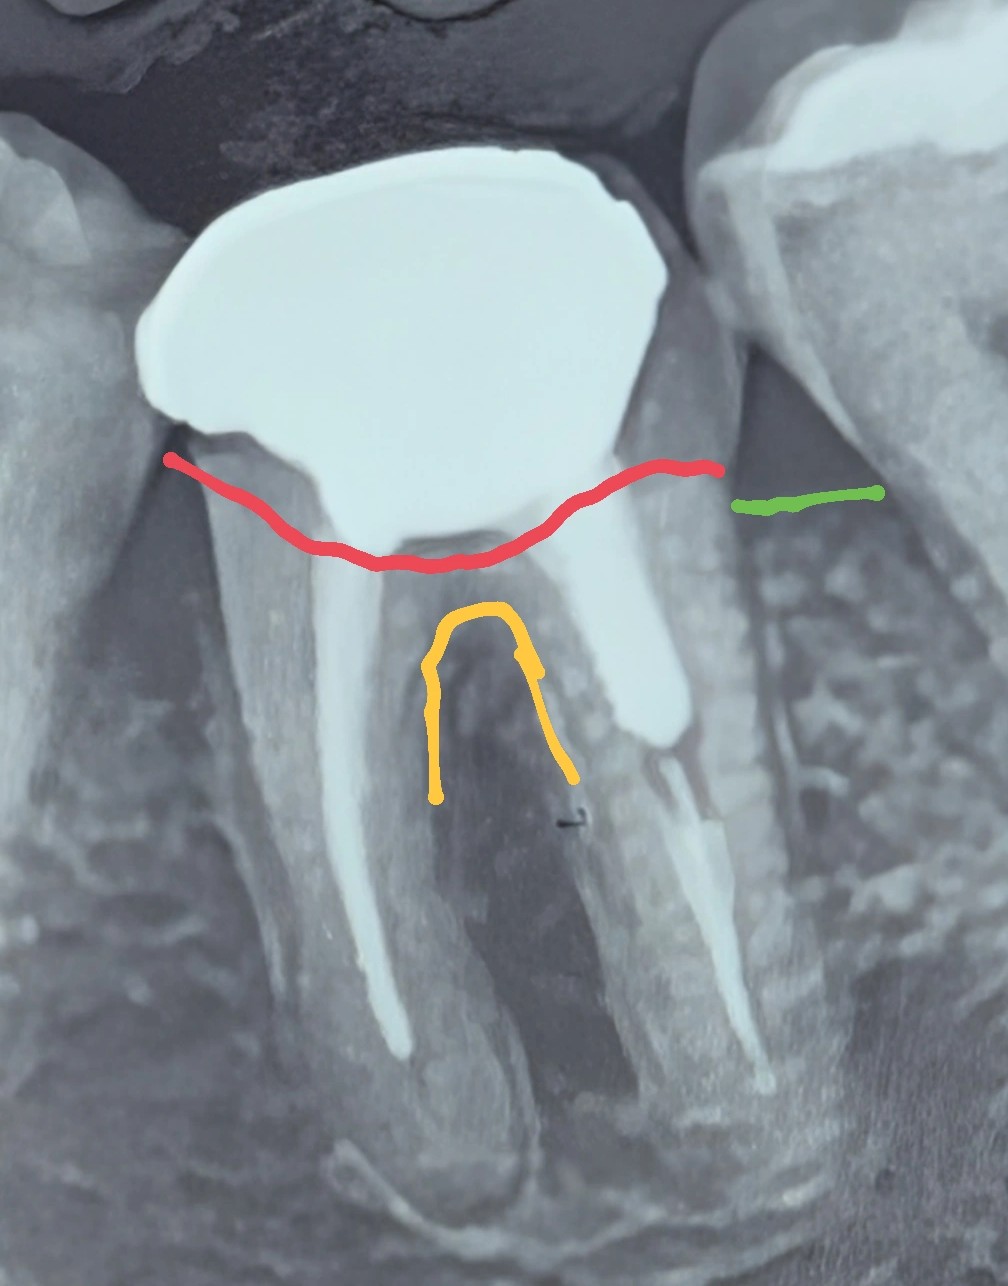

در این کیس، یک مولر پایین چپ با تخریب گستردهٔ ساختار و مشکلات درمان ریشه مشاهده میشود. تحلیل دقیق رادیوگرافی و معاینهٔ کلینیکی موارد زیر را مشخص میکند:

مرز پوسیدگی (خط قرمز) در تصویر نشاندهندهٔ تخریب وسیع است، اما در رادیوگرافی عمق و وسعت واقعی پوسیدگی کمتر از مقدار حقیقی دیده میشود.

طبق خط سبز (سطح استخوان)، ارتفاع نسج باقیمانده برای ایجاد bw مناسب کافی نیست.

هر نوع تلاش برای ایجاد فضای bw با جراحی افزایش طول تاج، به دلیل میزان تخریب موردنیاز روی استخوان، ما را در محدودهٔ فورکا قرار میدهد.

در تصویر:

- کانالها بهطور کامل و استاندارد پر نشدهاند

- نیاز به retreatment وجود دارد